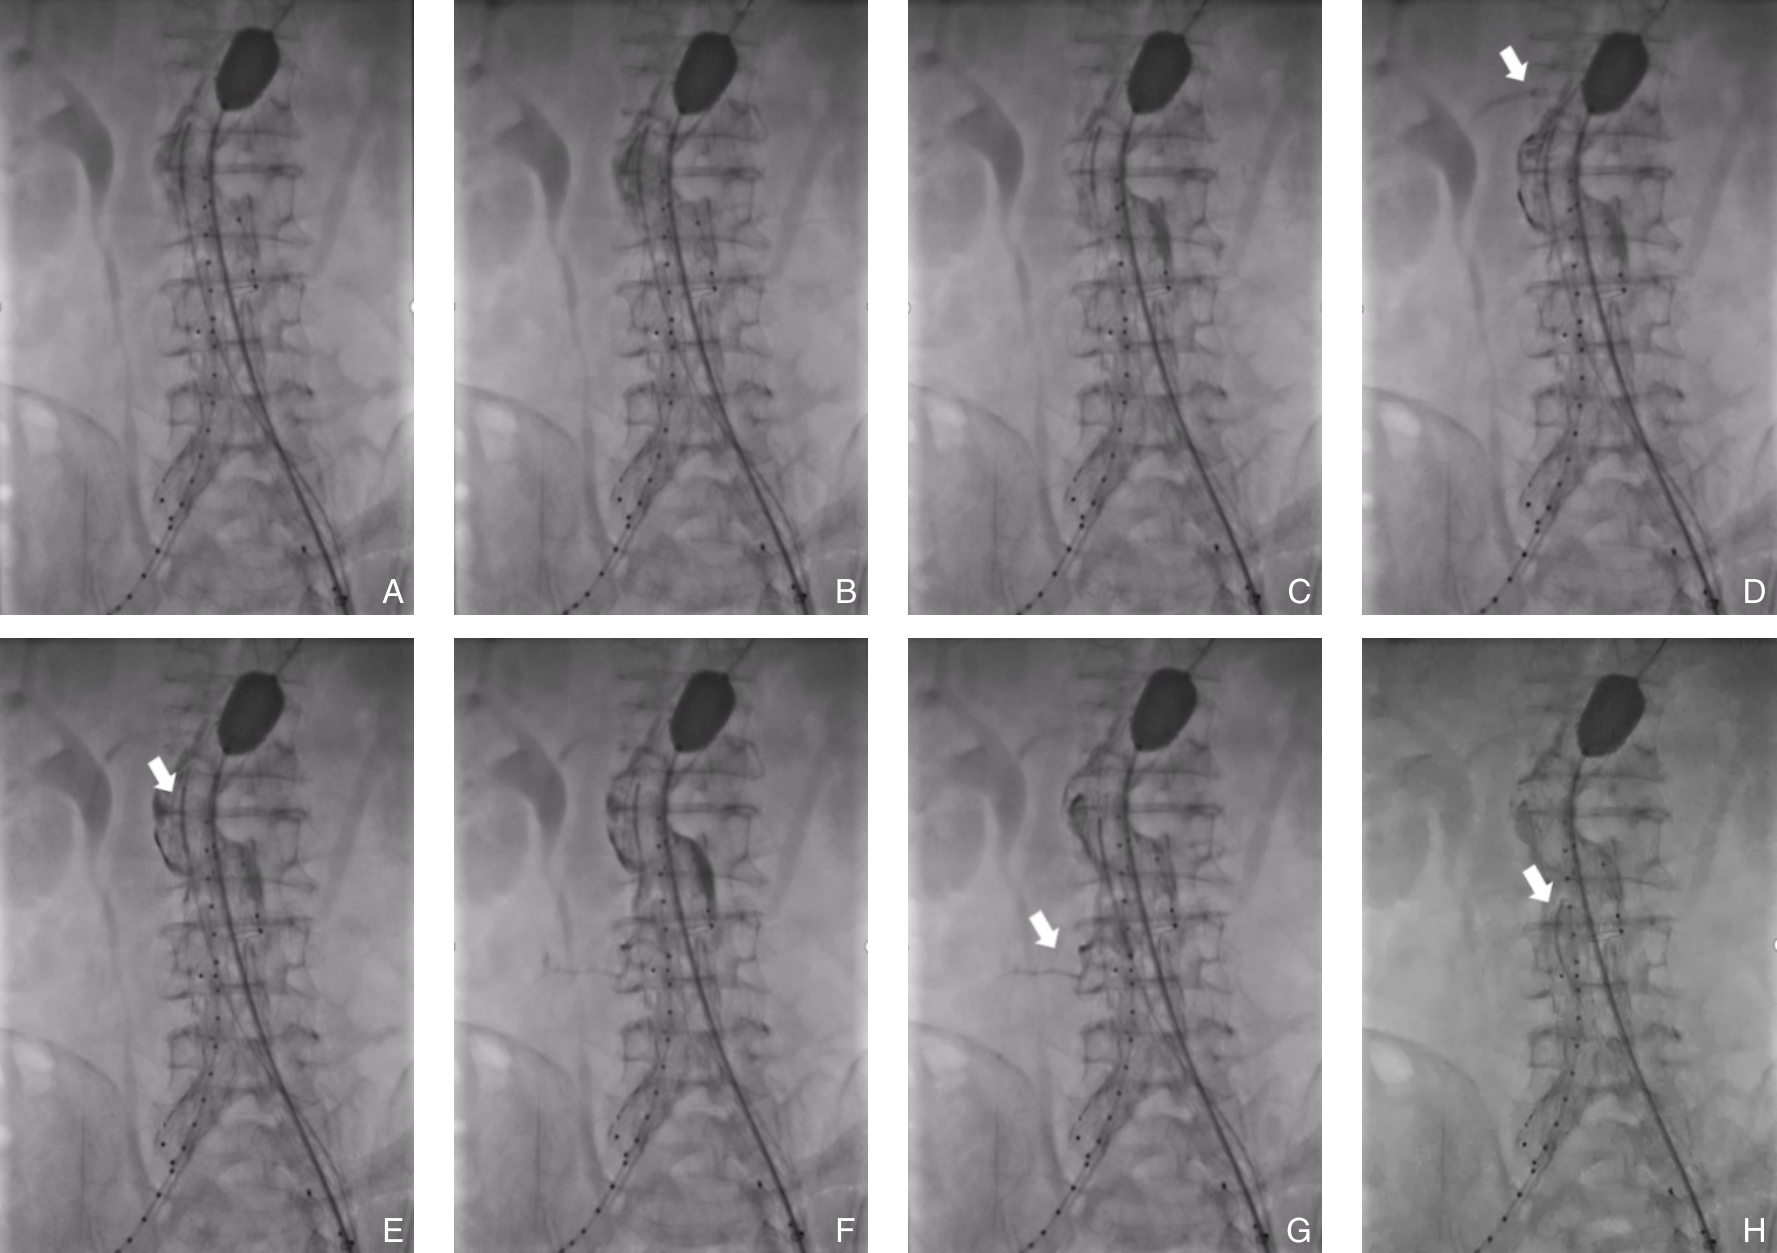

Abdominal aortic aneurysm is a potentially fatal vascular disease commonly encountered in the elderly population. Although endovascular aneurysm repair (EVAR) has become the preferred treatment modality, the incidence of postoperative endoleaks remains high (20%-40%), with more than 30% of cases requiring secondary interventions, thereby significantly compromising long-term outcomes. To standardize the application of fibrin sealant aneurysm sac filling during EVAR, the Vascular Surgery Professional Committee of the Chinese Association of Rehabilitation Medicine convened a multidisciplinary expert panel. In accordance with the RIGHT reporting guideline and the GRADE evidence grading system, and through two rounds of Delphi surveys to prioritize clinical questions combined with systematic evidence review, the committee developed the Expert consensus on fibrin sealant aneurysm sac filling during endovascular abdominal aortic aneurysmal repair. This consensus systematically addresses key aspects including indications and contraindications, technical procedures, dosage estimation, intraoperative assessment criteria, prevention and management of complications, and postoperative follow-up. It defines criteria for complete sac filling and provides tailored application strategies under various anatomical conditions. The aim of this consensus is to standardize clinical practice, reduce the incidence of endoleaks, improve long-term outcomes after EVAR, and provide vascular surgeons with evidence-informed and practically applicable guidance.

-